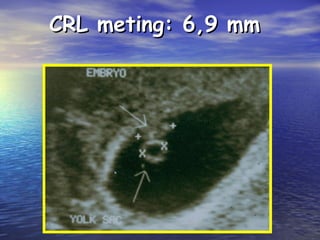

CRL meting: 6,9 mmCRL meting: 6,9 mm